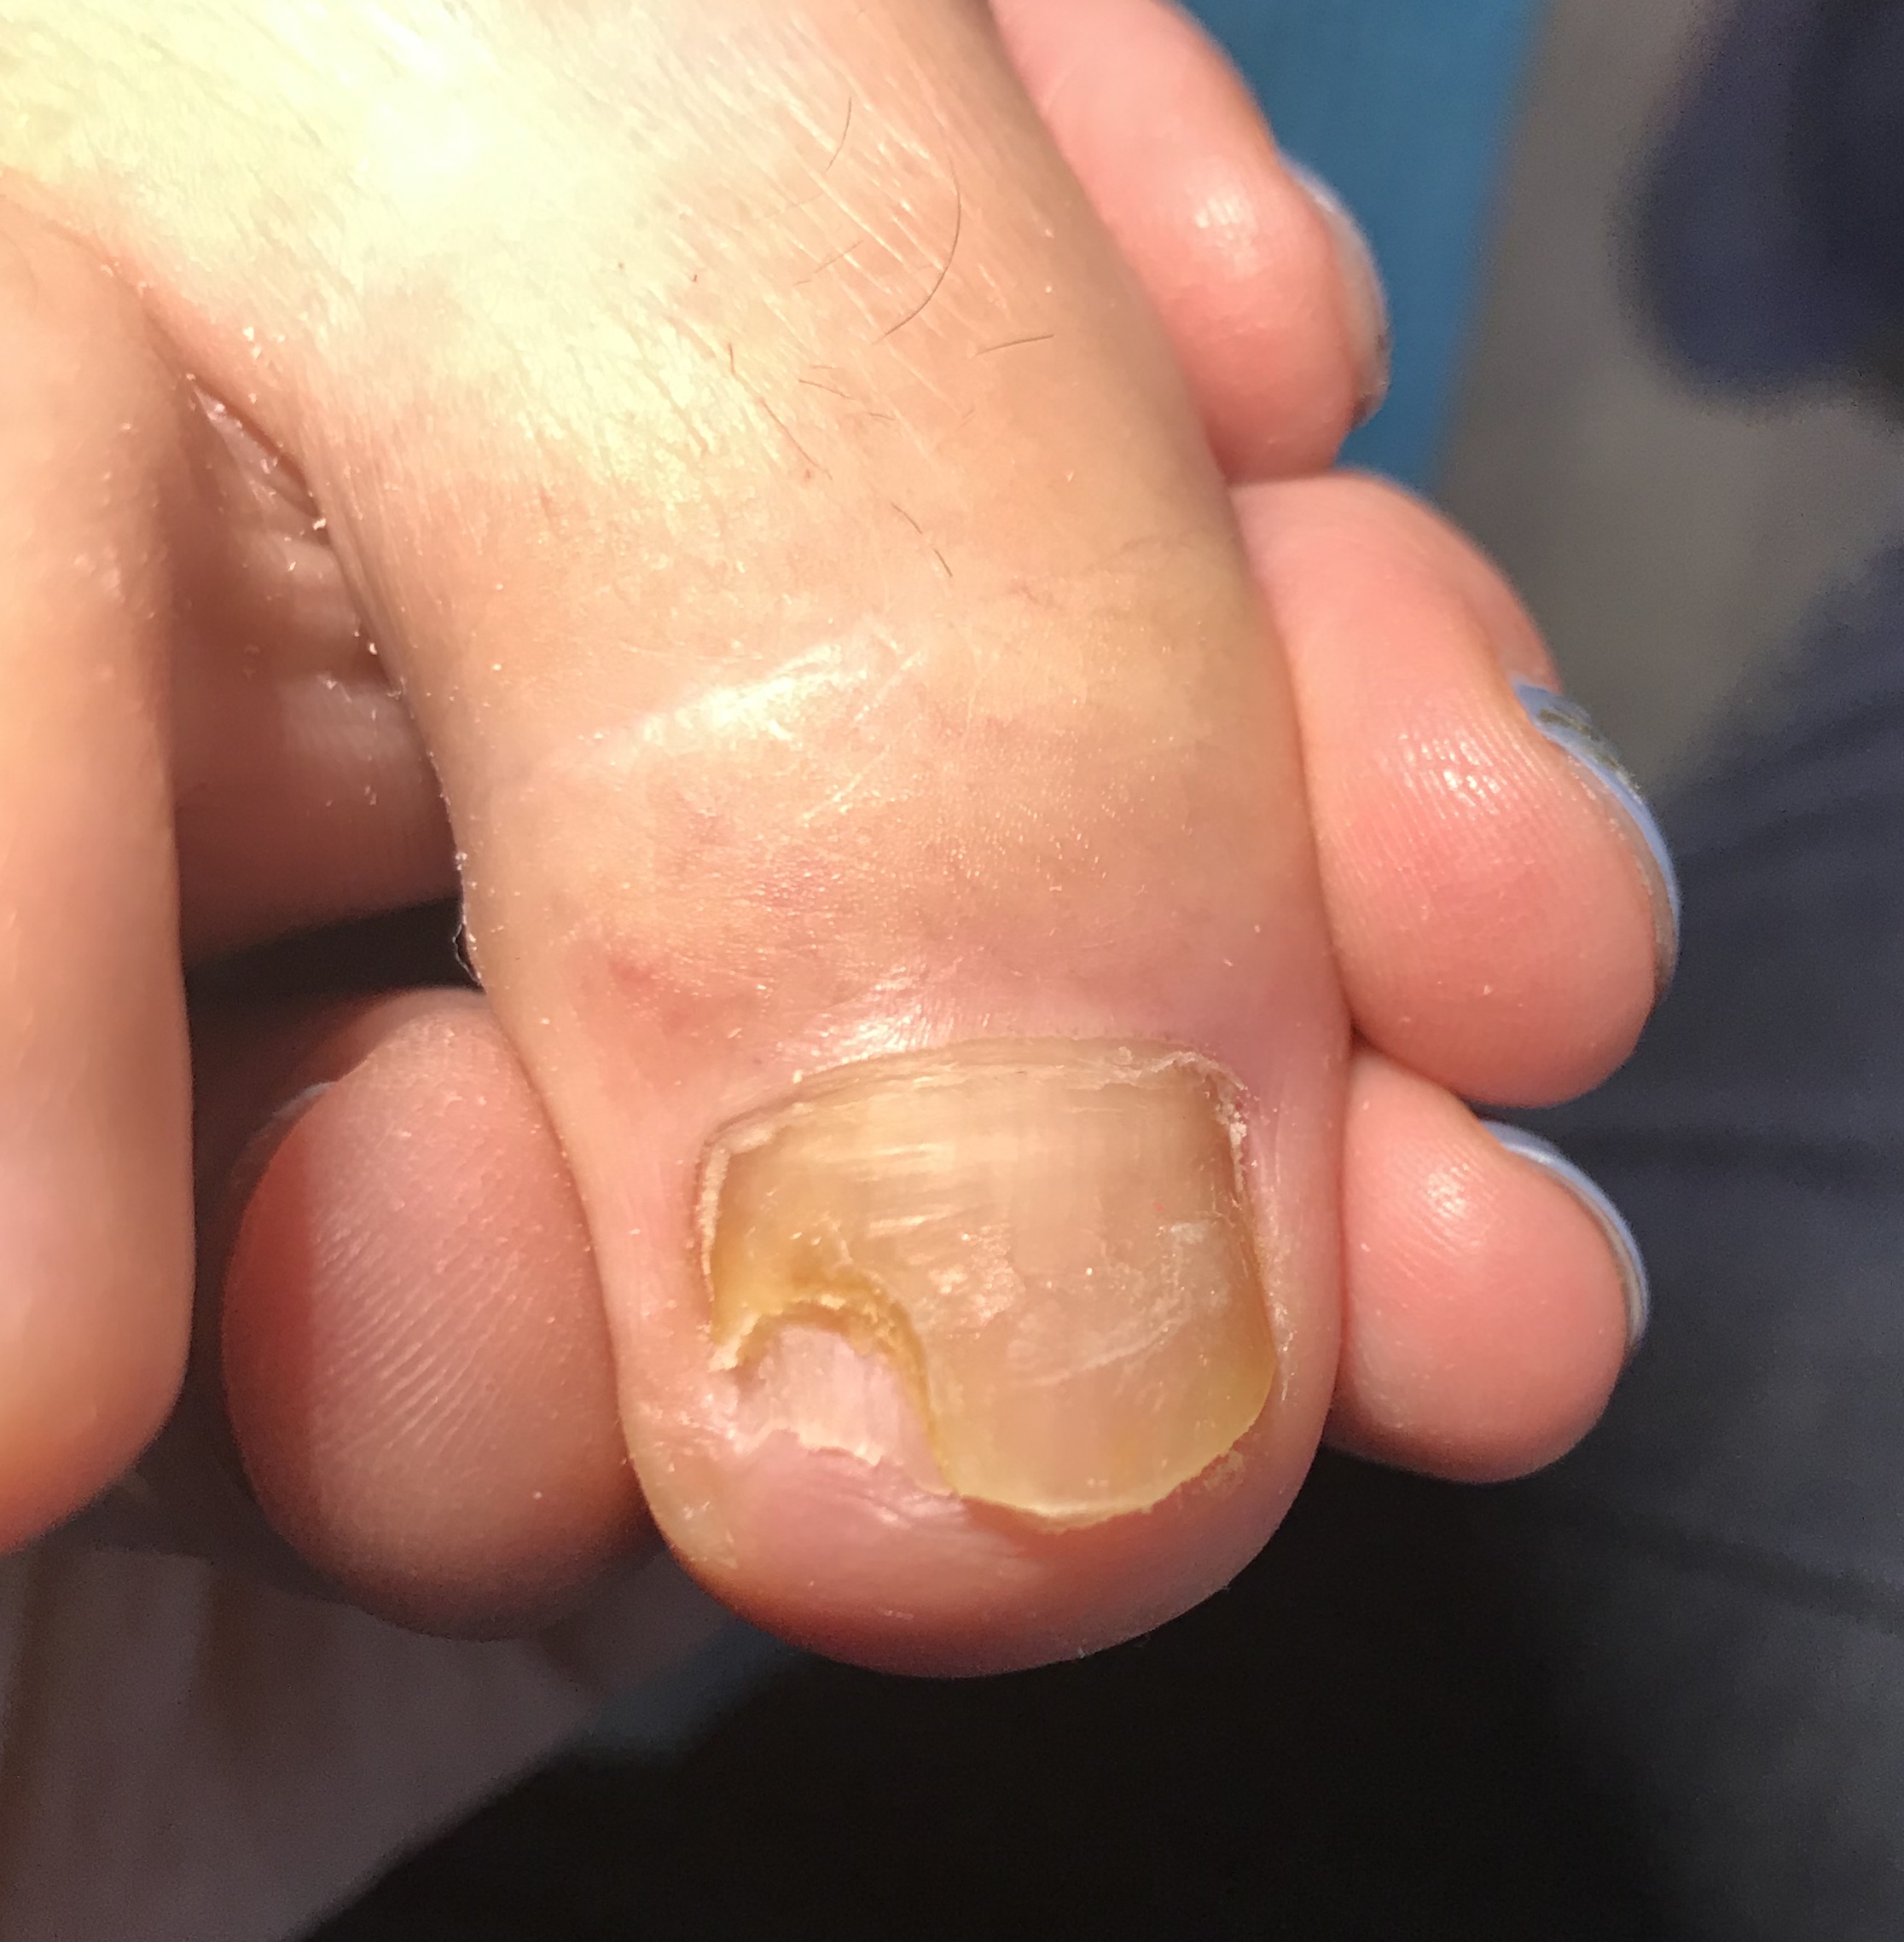

Mycose